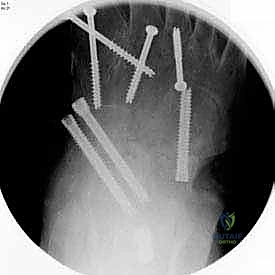

5. التثبيت الداخلي (Internal Fixation)

بعد التأكد من الوضعية المثالية للعظام، يتم تثبيتها بقوة باستخدام مسامير معدنية مجوفة من التيتانيوم (Cannulated Screws) أو شرائح معدنية خاصة. يتم إدخال المسامير تحت توجيه الأشعة السينية المباشرة (Fluoroscopy) داخل غرفة العمليات لضمان الدقة المتناهية. هذه المسامير تضغط العظام معاً وتمنع أي حركة حتى يحدث الالتئام التام.

- يتم إجراء أشعة سينية للتأكد من بدء تكون الكالس العظمي (Bone Callus).

- إذا أظهرت الأشعة التئاماً جيداً، يبدأ الدكتور هطيف بالسماح بتحميل الوزن التدريجي (Partial Weight Bearing) أثناء ارتداء الحذاء الطبي.